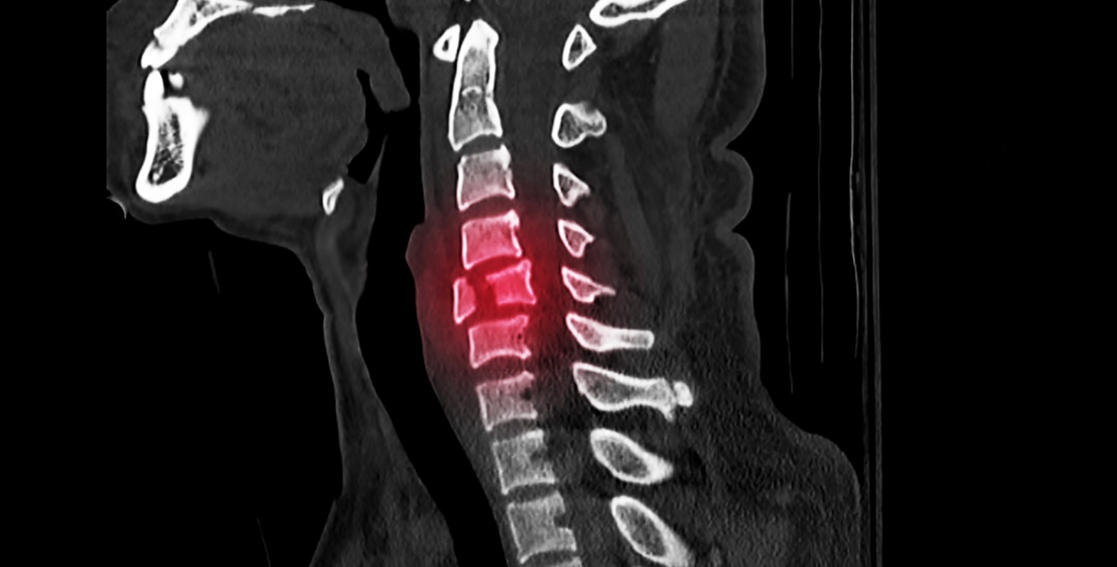

脊髓损伤(SCI)是由于创伤导致的脊髓结构破坏,引起感觉、运动和自主神经功能障碍。该病每10万人年发病率达13例,可导致部分或完全性瘫痪,严重影响患者生活质量并给社会带来了巨大经济负担。

脊髓损伤